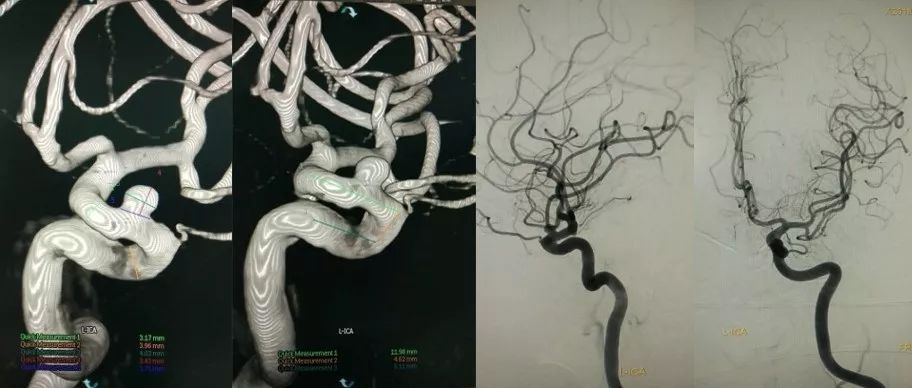

患者 女 64岁 双侧颈内动脉瘤

左侧瘤体4.03mm*3.43mm,载瘤动脉近远端最大径约3.17mm,3.96mm。

右侧床突段相邻1大1小两个动脉瘤,大瘤体16.95mm*12.61mm,瘤颈5.99mm,载瘤动脉近远端最大径约3.97mm,4.66mm; 小瘤体2.85mm*3.24mm, 载瘤动脉近远端最大径约4.34mm,3.24mm;Tubridge拟覆盖范围需跨越两个瘤颈,长度约24.32mm。